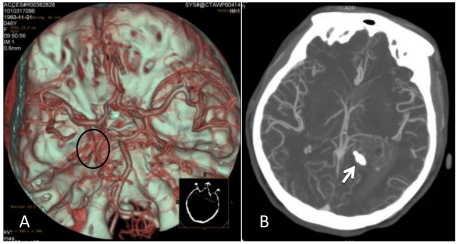

Figure 2.

CTA after the onset of intraventricular hemorrhage. A: No intracranial artery malformation was observed; medial blood vessels of the tumor in the trigone of the lateral ventricle were disordered, and the tumor was supplied by anterior and posterior choroidal arteries (oval area). B: Maximum intensity projection revealed a high-density shadow in the trigone of the left lateral ventricle; the surrounding vessels were disordered, and a high-density calcification shadow was detected at the rear of the lesion (arrow).